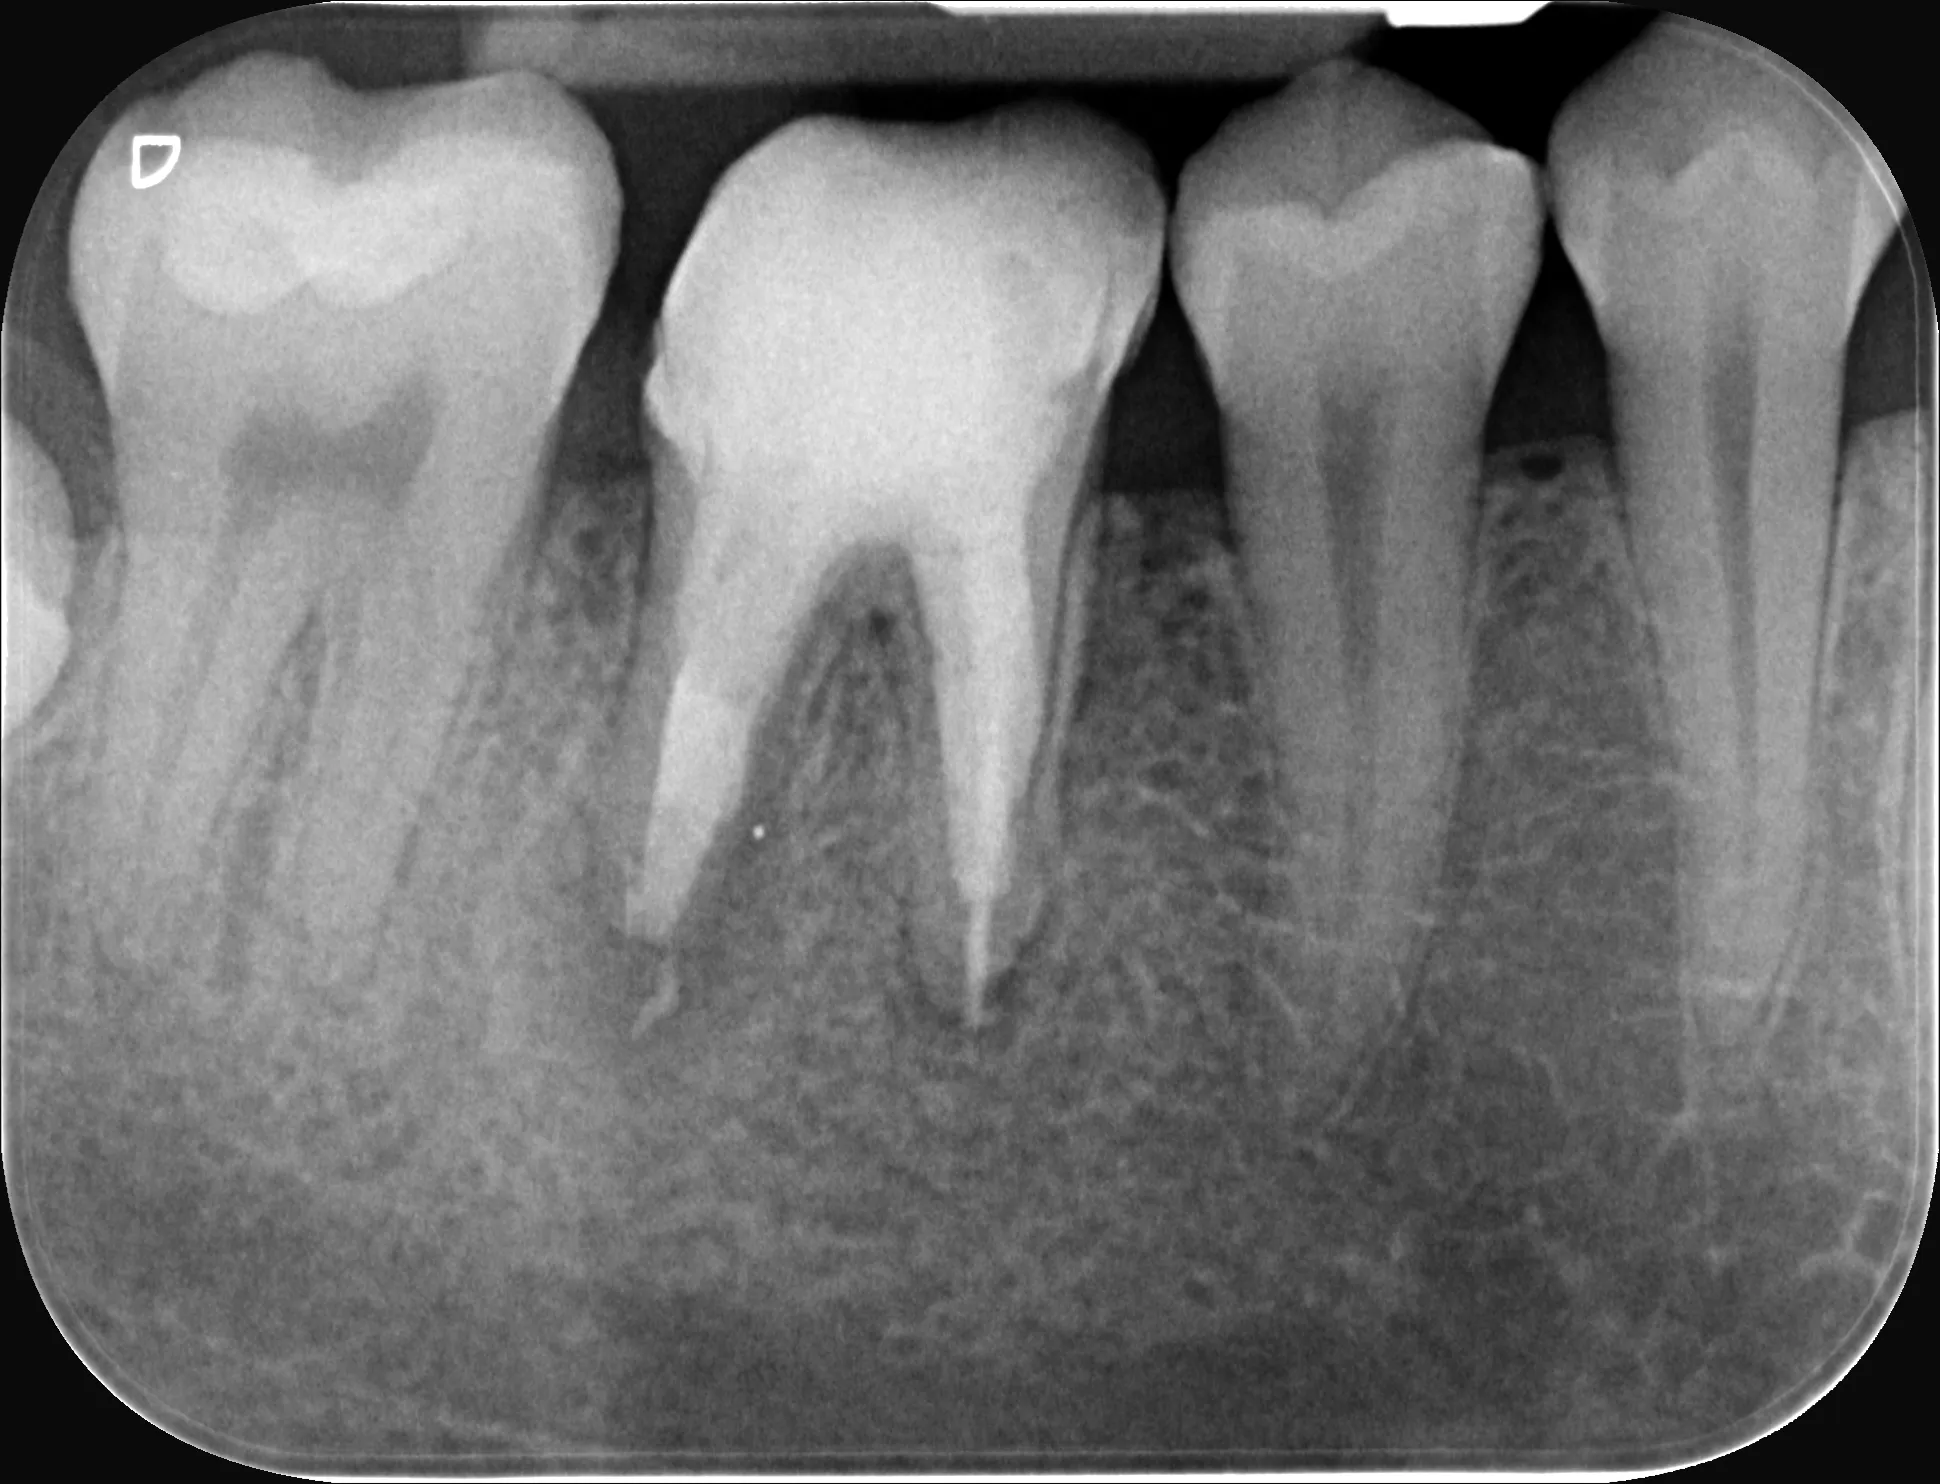

0 – Radiografie inițială